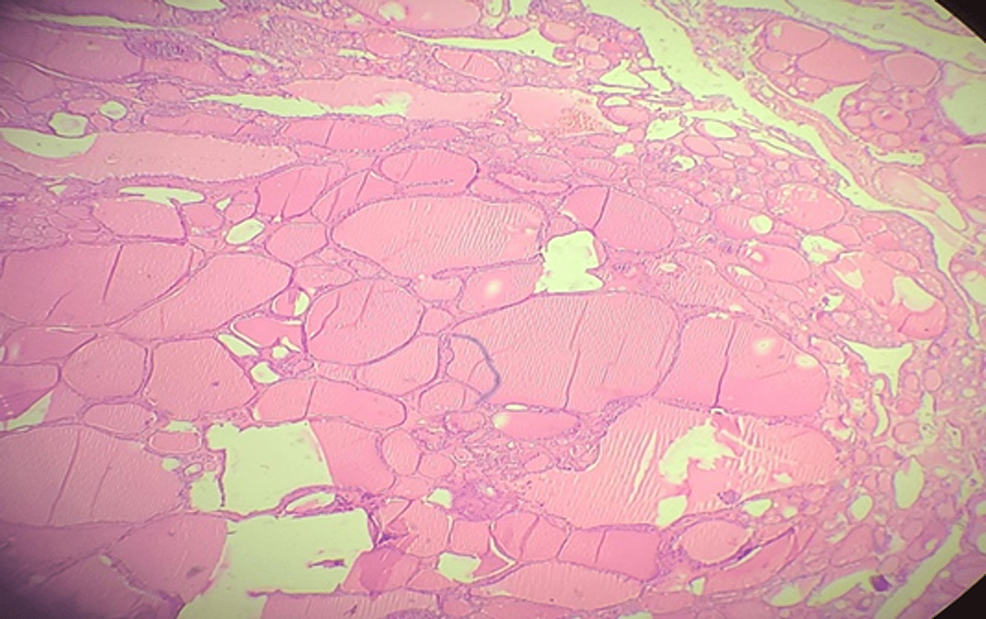

After proper optimization and pulmonology, cardiology, and anesthesia clearance, the patient was taken up for right submandibular sialadenectomy. A right submandibular transverse incision, 2cm below the mandible was made. The right submandibular gland was found to be enlarged and infiltrating the surrounding structures. Sialadenectomy was done, hemostasis was attained, no. 10 drain was introduced, and the skin was closed in layers. The biopsy of the operative sample showed nodular colloid goiter with no metastatic foci in any sample and chronic sialadenitis which is a rare presentation (Figure 3).

The diagnosis of ETT is confirmed by the biopsy of the operative specimen. The different imaging modalities and clinical tests often fail to differentiate between a benign and a malignant ETT [10]. The usually performed radiological investigations such as USG and CT scan help in describing the extent, location, and consistency of the mass, but a biopsy is mandatory for confirming the diagnosis. A thyroid function test should be done both pre-operatively and post-operatively and is an essential test that should be mandatory in all cases of ETT [11]. In our case on FNAC, features of basaloid neoplasm like pleomorphic adenoma were seen as the lesion was evaluated as a submandibular mass and not thought of as a thyroid lesion at all. No thyroid tissue was obtained in FNAC; hence, The Bethesda System for Reporting Thyroid Cytopathology (TBSRTC), which consists of the following categories: I – non-diagnostic, II – benign, III – atypia of undetermined significance (AUS)/ follicular lesion of undetermined significance (FLUS), IV – follicular neoplasm/suspicious for follicular neoplasm (SFN), V – suspicious for malignancy, and VI – malignant; is not applicable here. Clinically it was not thought of as a case of ETT, instead was considered as a lesion of the submandibular gland. CECT was also pointing toward a malignant lesion of the submandibular gland, such as adenoid cystic carcinoma. FNAC was misleading as no thyroid tissue was obtained and showed features of a basaloid neoplasm. Finally, the definitive diagnosis of ETT was made from the histopathological examination of the operative specimen, which showed chronic sialadenitis with nodular colloid goiter with no metastatic foci.